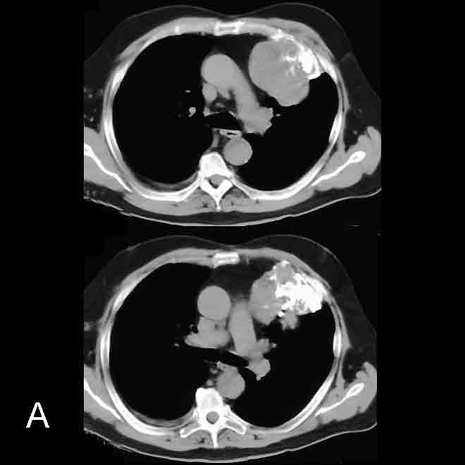

Image A shows an unlabeled CT image.

Image B shows the chondrosarcoma originating in an anterior left upper rib, outlined in red.  The mass contains considerable calcification, with a somewhat swirling shape that is characteristic of lesions arising from cartilaginous cells, shown in blue.